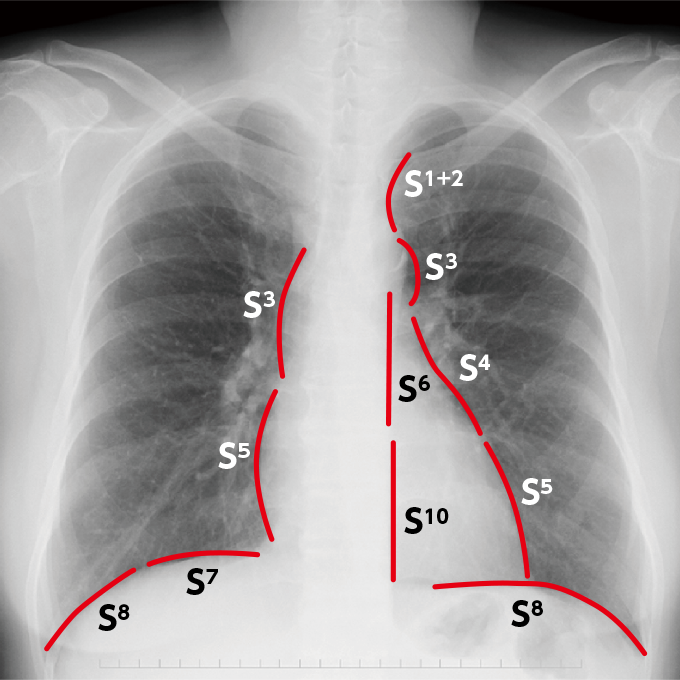

肺区域の解剖(図2)を踏まえたうえで、X線画像をみると、心臓、大動脈、横隔膜と接する肺区域がそれぞれわかってくる。

図2肺区域

心臓は解剖学的に縦隔前面に位置しており、S4、S5と接することになる。大動脈弓は後ろにあるため、S6、S10と接しており、横隔膜は前方から後方にかけて位置しているため、S7,S8と接していることがわかる(写真2)。

写真2臓器と接するそれぞれの肺区域

接している部分の境界が不明瞭(シルエットサイン陽性)であればそこには何らかの生理的変化が生じているのではないかとアセスメントすることが重要である。